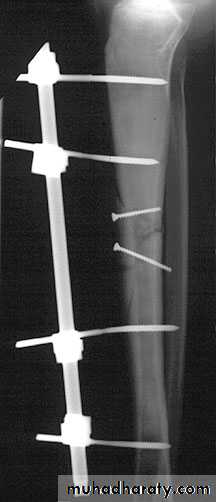

3-External fixation This is an alternative to closed nailing; it avoids exposure of the fracture site and allows further adjustments to be made if this should be needed.

Operative treatment

HIGH-ENERGY FRACTURES

Comminuted and segmental fractures, those associatedwith bone loss, and indeed any high-energy fracture

that is inherently unstable, require early surgical

stabilization. For closed fractures, external fixation

and closed nailing are equally suitable; in both cases

the tissues around the fracture are left undisturbed.